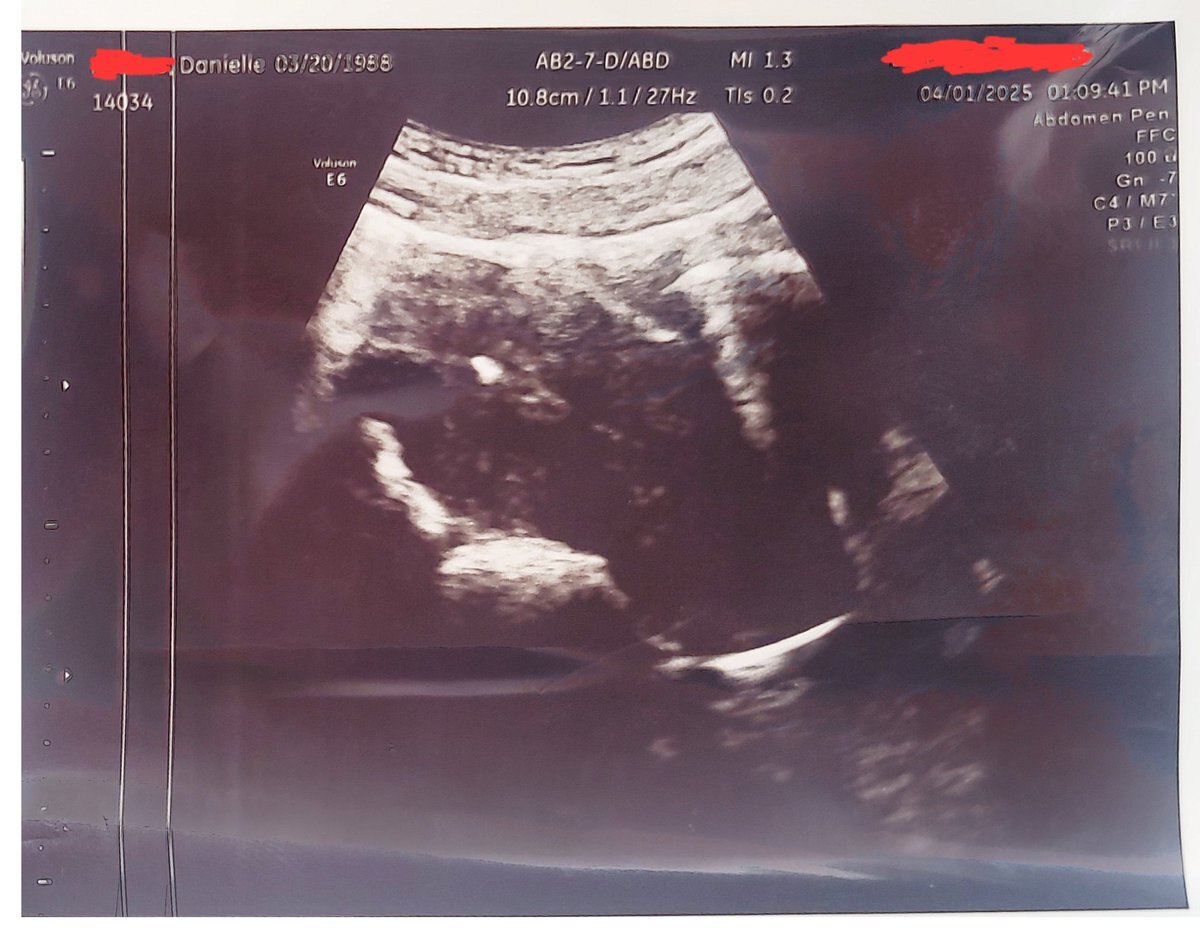

> I'm pregnant!